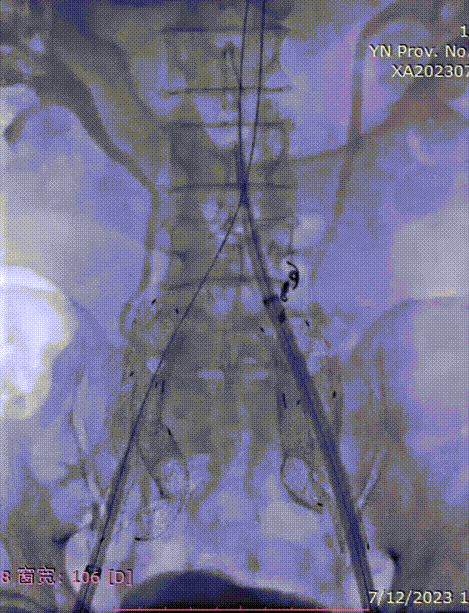

植入腹主动脉主体支架

完成双侧IBE植入后,按术前计划,从右侧送入腹主动脉主体支架。

• 造影确认主体支架植入位置;

• 释放主体支架至短腿弹出。